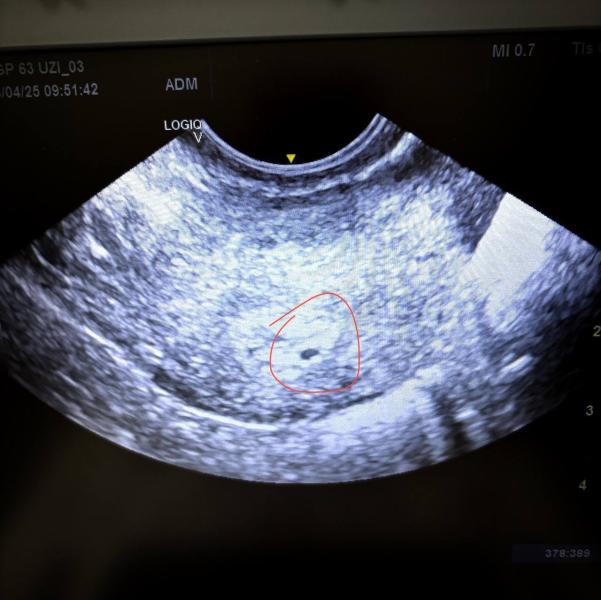

С сыном получилось за 2,5 месяца, и я надеялась, что теперь всё тоже случится быстро. Так и вышло - 24 апреля я держала в руках заветный тест с двумя полосками А уже 28-го сообщила о нем врачу,а на УЗИ было видно крошечное плодное яйцо, всего 3 мм!

На фото первые тесты с призраками и первое узи.К сожалению, психанув, я выкинула снимки платного узи и удалила всё связанное с тем периодом.

Чтобы успокоиться, 5 мая я пошла на платное УЗИ. И, к сожалению, мои страхи подтвердились - плодное яйцо всё то же, 3 мм. За неделю должно было вырасти, но не выросло.